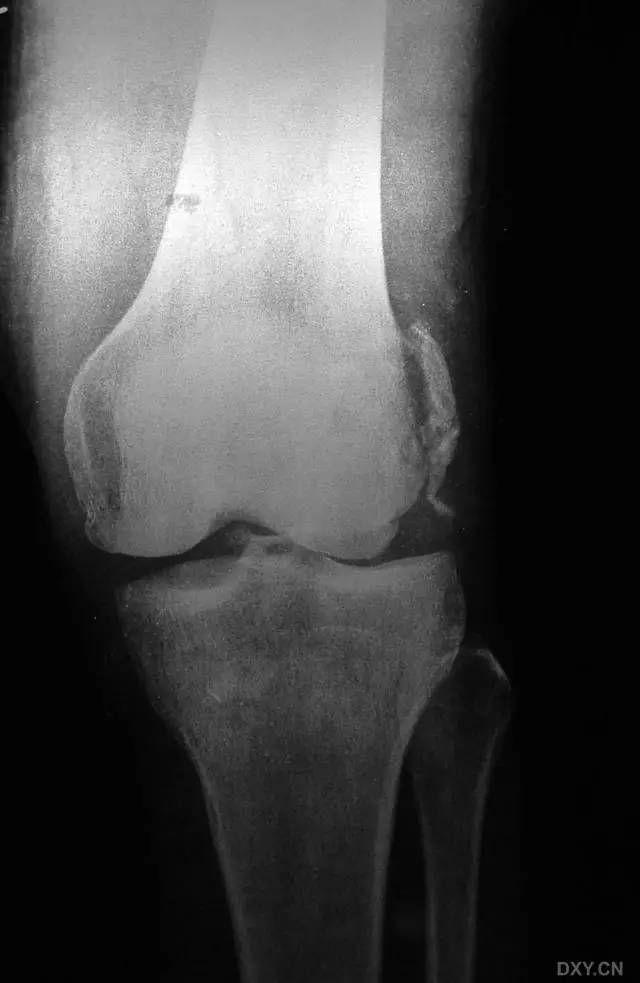

8. Segond 骨折和反向 Segond 骨折

(1)Segond 骨折

是发生在胫骨平台外侧的垂直撕脱性骨折。这种骨折在前后位 X 线片上显示最佳。屈曲位时膝关节受到内旋暴力作用,导致皮质骨撕脱性骨折,这种骨折常发生在运动员身上。

常引起股骨内髁和胫骨平台后内侧骨挫伤,75%~100% 的患者伴前交叉韧带断裂,33% 的患者伴外侧半月板损伤。

一位足球运动员的 Segond 骨折。A 正位片示关节线下方胫骨外侧皮质撕脱(箭头)。B MRI 冠状位 T1 加权像示附着于髂胫带的骨折碎片(空箭头)(来源:Radiol Clin N Am 53 (2015) 737–755,YU,Ohio)

(2)反向 Segond 骨折

胫骨平台内侧皮质骨撕脱性骨折,被称为内侧 Segond 骨折或反向 Segond 骨折。这种骨折的旋转机制与 Segond 骨折相反,该骨折与后交叉韧带断裂及内侧半月板损伤相关。

一位足球运动员的反向 Segond 骨折。A 正位片示关节线处的胫骨内侧见一细小骨折片(箭头)。B MRI 冠状位 T1 加权像示骨折片出现在内侧副韧带关节囊附着处(方框)(来源:Radiol Clin N Am 53 (2015) 737–755,YU,Ohio)